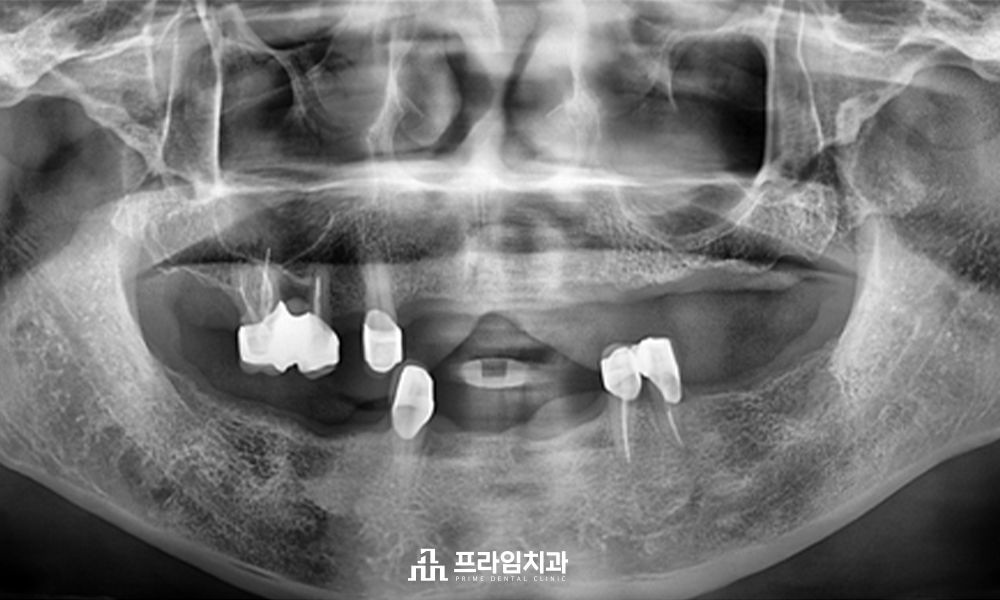

엑스레이 사진을 살펴보면

상하 치아가 몇 개 남지 않은 상황입니다.

현재 사용 중인 틀니는 남아있는

치아에 걸쳐 사용하는 부분틀니입니다.